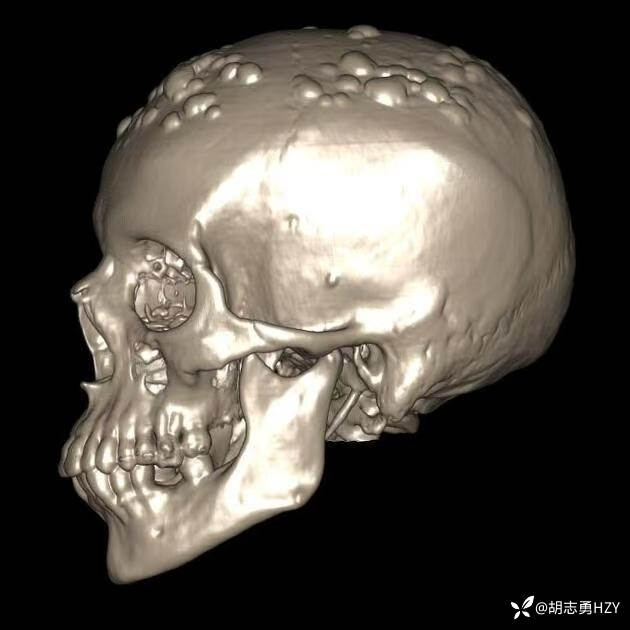

女性,45岁,家族性腺瘤性息肉病,额部顶部多发无痛性硬质包块(2025 1108)

女性,45岁,家族性腺瘤性息肉病,额部顶部多发无痛性硬质包块